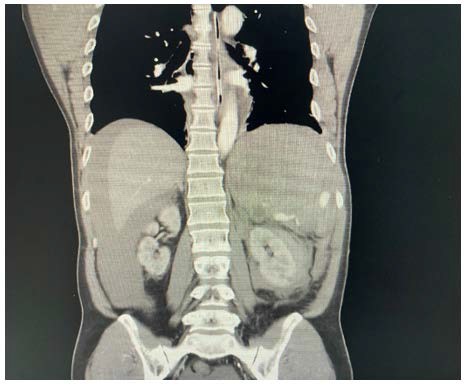

In this case, although eFAST showed free fluid in Morrison’s pouch and splenorenal recess, it failed to localize the bleeding source, demonstrating its limitations in retroperitoneal trauma. This supports the need for clinicians to escalate to WBCT imaging when eFAST findings are inconclusive and clinical suspicion remains high (Figure 1 & Figure 2).

Figure 1: Mass Showing in Mixed Echogenicity

Figure 2: Free Fluid Over Splenorenal Recess